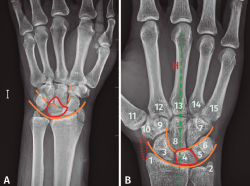

Figura 4. A: radiografía anteroposterior de luxación transestiloperilunar; B: radiografía anteroposterior sin alteraciones, recuerdo anatómico. 1: estiloides radial; 2: estiloides cubital; 3: escafoides; 4: semilunar; 5: piramidal; 6: pisiforme; 7: ganchoso; 8: grande; 9: trapecio; 10: trapezoide; 11: primer metacarpiano; 12-15: segundo a quinto metacarpianos; —: almohadilla grasa; —: eje longitudinal 3.er radio, muñeca y antebrazo; —: arcos de Gilula.

- Qué ver en una radiografía anteroposterior de muñeca (Figuras 4A y 4B). Para valorar que estamos ante una correcta proyección, debemos obtener:

– Una vista anteroposterior de la región media de los metacarpianos, del carpo, de la articulación radiocubital distal.

– La forma de la diáfisis de los metacarpianos debe ser cóncava.

– Debe existir una separación del radio y cúbito distales (puede existir una superposición mínima).

– Por último y más importante, el eje longitudinal del 3.er radio, la muñeca y el antebrazo deben quedar alineados.

En la radiografía podemos observar los siguientes ítems:

– Observar la alineación correcta de las articulaciones.

– Buscar interrupciones en las corticales de los huesos que nos puedan hacer sospechar una fractura.

– Afectación intraarticular.

– Pero, en especial, debemos fijarnos en los arcos de Gilula, deben formar 3 líneas continuas, sin disrupciones. En las luxaciones se pierde la continuidad de las líneas que forman los diferentes arcos.

- 1.er arco: superficie proximal del escafoides, semilunar y piramidal.

- 2.º arco: superficie distal del escafoides, semilunar y piramidal.

- 3.er arco: superficie proximal de grande y ganchoso.